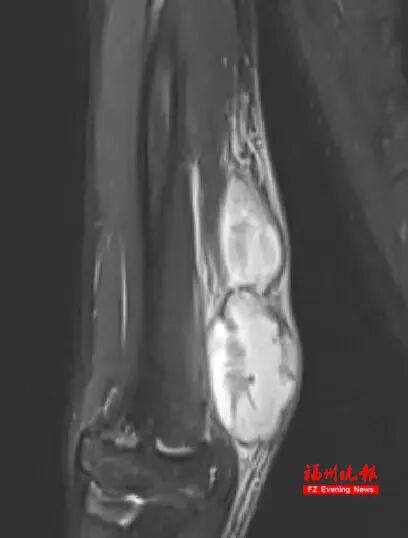

接诊小宇的是林佳生副主任医师,他经过仔细查看比对,发现小宇的病灶与典型恶性肿瘤有差异,更倾向感染性或血液系统疾病。于是,他立即为小宇完善磁共振检查,并与影像科医生共同阅片,认为影像表现支持猫抓病可能。而且追问病史得知,小宇常喂小区流浪猫,医生由此怀疑可能是猫抓病。

尽管如此,林佳生并未放弃:“临床症状、病史与影像特征高度契合猫抓病,不能因单一检查阴性就排除。”随即他邀请感染科开展多学科会诊,最终决定采用阿奇霉素+利福平进行经验性治疗。令人欣喜的是,出院1个月后复查,小宇手臂的“大瘤子”已完全消失,磁共振显示病灶明显缩小,家长连连向医护团队致谢。